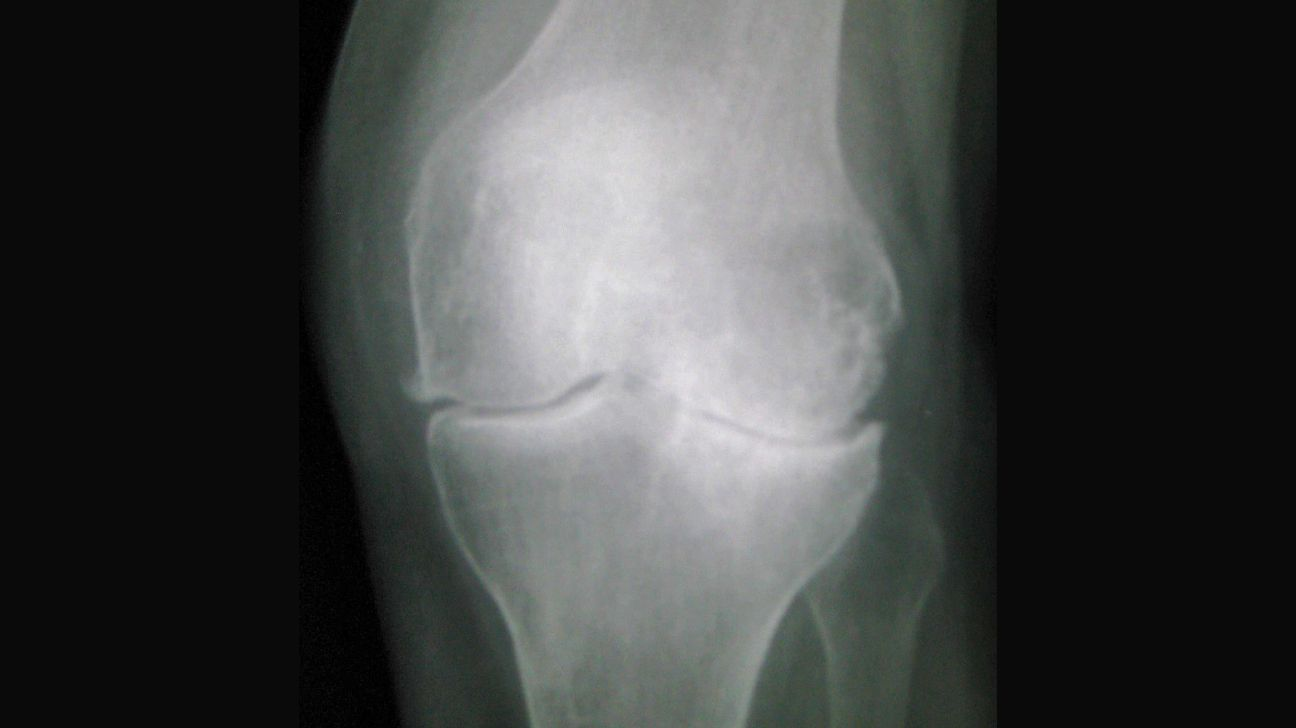

膝关节自救:膝骨关节炎的X光片分级解读与运动、体重管理

报告解读 付费

你的膝盖可以更好,而不是只能变差! 想象一下:3个月后,你可以轻松上下楼梯;6个月后,你可以去游泳、骑车、旅行;1年后,你甚至可能忘记自己曾经有过膝关节炎——...

2026/1/22